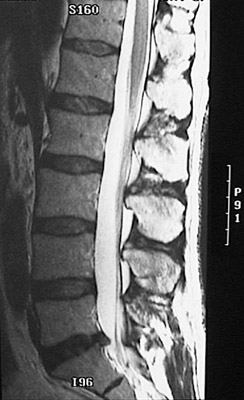

This MRI of the spine demonstrates herniation of the nucleus pulposis of the intervertebral disc between L5 and S1 with compression of the lumbar spinal cord. Such a herniated disc can compress spinal nerve roots to produce pain and/or motor weakness. In the transverse view below, the herniation is seen to compress the nerve roots on the left. |